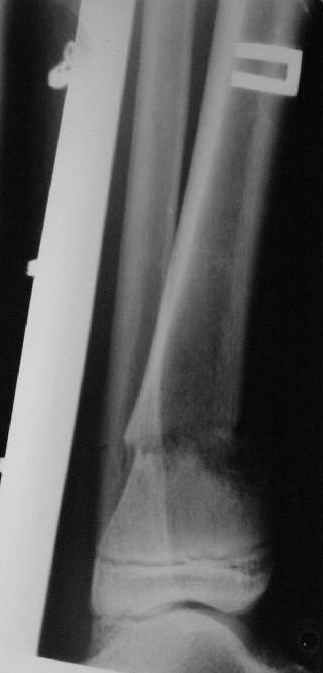

Фиксация

|

в гипсе